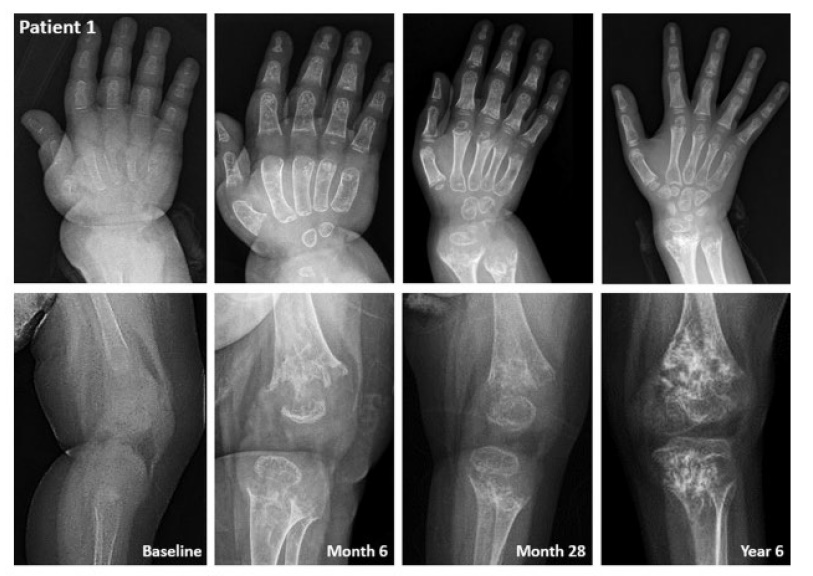

- 생후 8일에 청색증 동반한 전신 강직성 발작과 호흡 곤란을 보여 신생아 중환자실로 입원함

- 골격 검사에서 전신성 골감소증 등의 골격 문제를 보여 전원함

- 생후 21일차에 HPP 진단되어 생후 30일에 스트렌식 치료를 시작함

- 증상이 케이스1보다 더욱 심각했음에도 불구하고, 빠르게 치료를 시행한 덕분에 치료 2개월 후 인공호흡기 사용 중단했으며, 골격 회복이 빠르게 이뤄짐

- 3년 차에는 구루병 소견을 보이지 않았으며, 정상 성장 곡선에 가까운 성장을 보임

- 최근 외래에서 뛸 정도로 보행 기능 개선을 확인함.